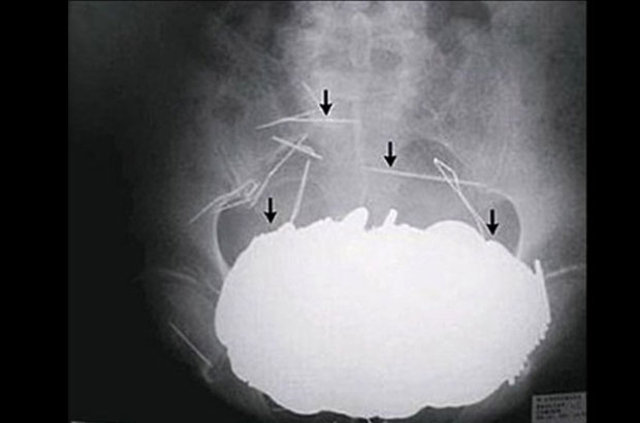

"Bu piller, özellikle yemek borusunda kaldığında saatler içinde ciddi yanıklara sebebiyet verebiliyor, mideye indiğinde etkileri o kadar olmasa da bu tür reaksiyonlar görülebiliyor. Pilli oyuncakları kullanırken çok dikkatli olmak gerekiyor.

Çocuğu yalnız bırakmamak gerekiyor. Çok güçlü mıknatıslar var, bunları sayıca fazla ya da metal cisimle yuttuklarında bunlar da birbiriyle yapışıp ciddi hasarlara yol açabiliyor.

Piller kimyasal mekanizmayla mukozayı yakıyor, özellikle yemek borusu çok duyarlı pillere, hele ki yeni takılmış bir pilse saatler içinde şahit olduğum bir kaç vaka var, yemek borusunu kömür haline getirebiliyor. Söz konusu cisimlerin yutulması durumunda en yakın sağlık kuruluşuna başvurulması gerekiyor."

Bir diğer sık karşılaştığımız durum ise pil yutmaları, bunlar yakıcı olduğu için bekleme süresinde 48 saati geçirmemeye özen gösteriyoruz. Pilin vücutta bulunduğu yer de müdahale etme koşullarını değiştirebiliyor.

Son olarak 9 aylık bir bebek pil yutma şikayetiyle getirildi. Pilin midede olmasına rağmen, yeni olması ve bebeğin yaşının küçük olması nedeniyle 3 saat içinde müdahalemizi yaptık endoskopiyle pili çıkarttık. Buna rağmen midede yanıklar vardı, bir süre hastamızı takip ettikten sonra taburcu ettik." (DHA)